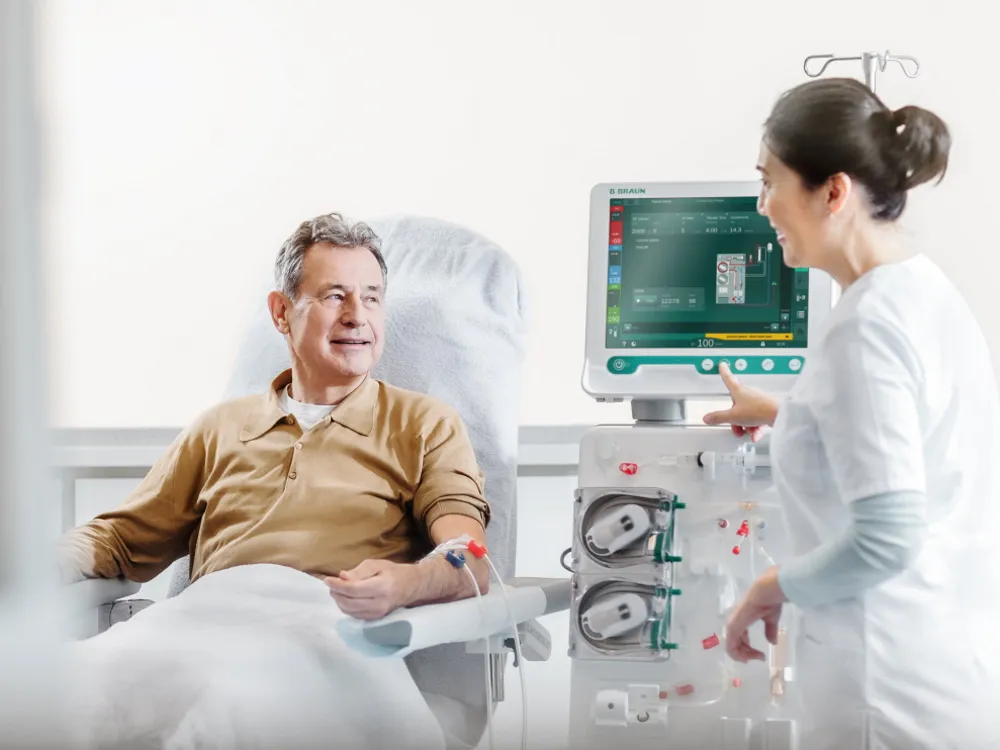

Ondansetrona e o risco de morte súbita em hemodiálise

Ondansetrona e o risco de morte súbita em hemodiálise

Como assim risco de morte súbita com Ondansetrona? Atenção especial aos pacientes com polifarmácia e risco de QT longo!